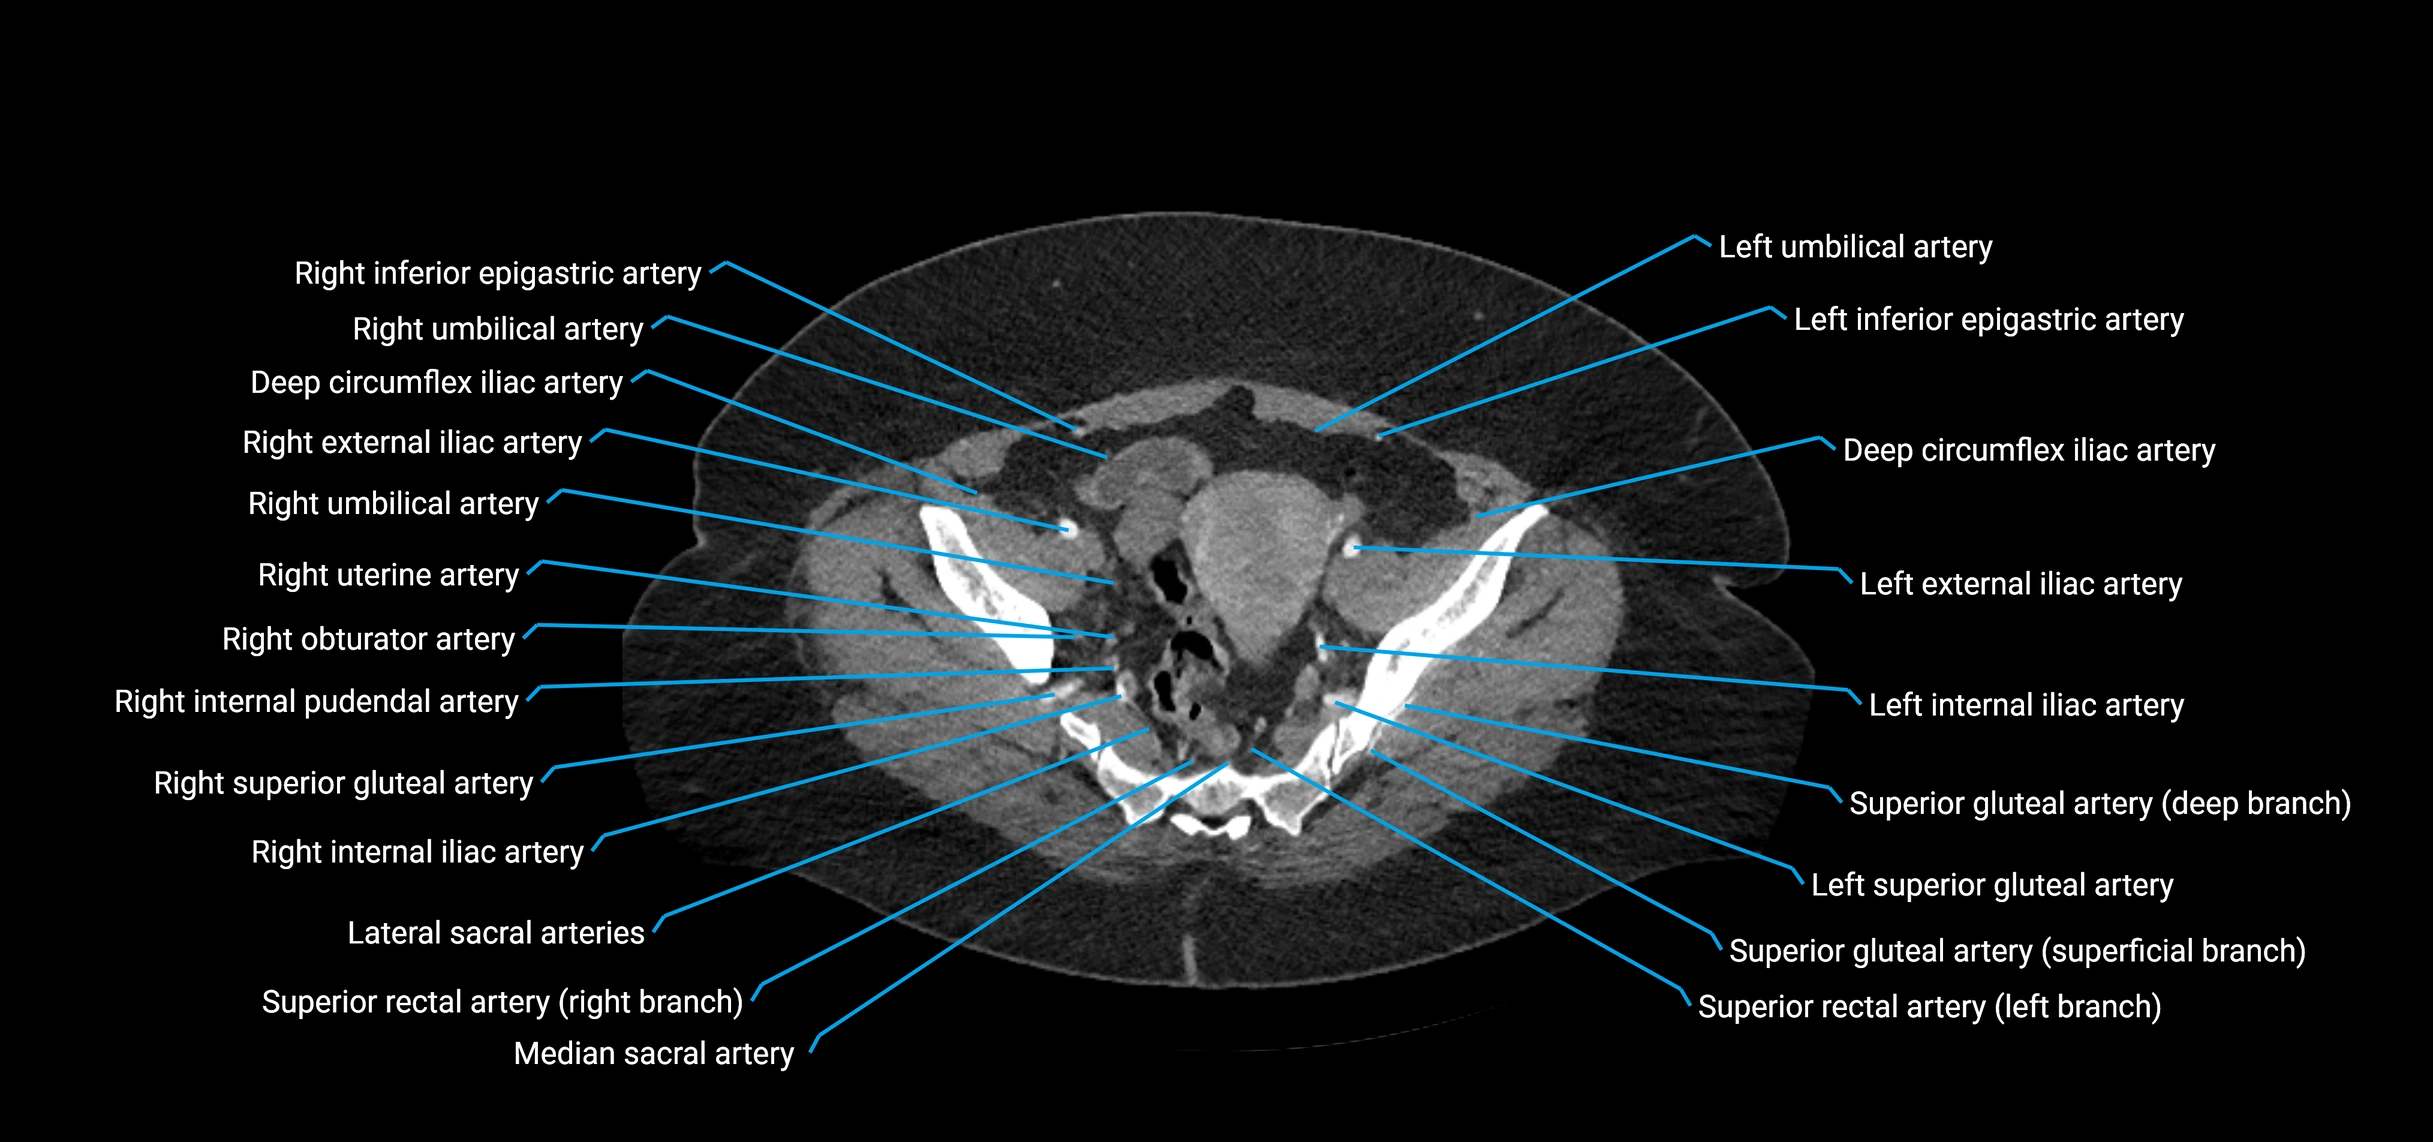

Contrast-enhanced CT (CTA):

• Gold standard for abdominal aortic imaging

• Provides excellent detail of lumen, wall, aneurysm, thrombus, and branch vessels

• Multiplanar and 3D reconstructions help in aneurysm measurement, stent graft planning, and dissection evaluation

• Detects acute rupture, traumatic injury, or occlusion with high sensitivity